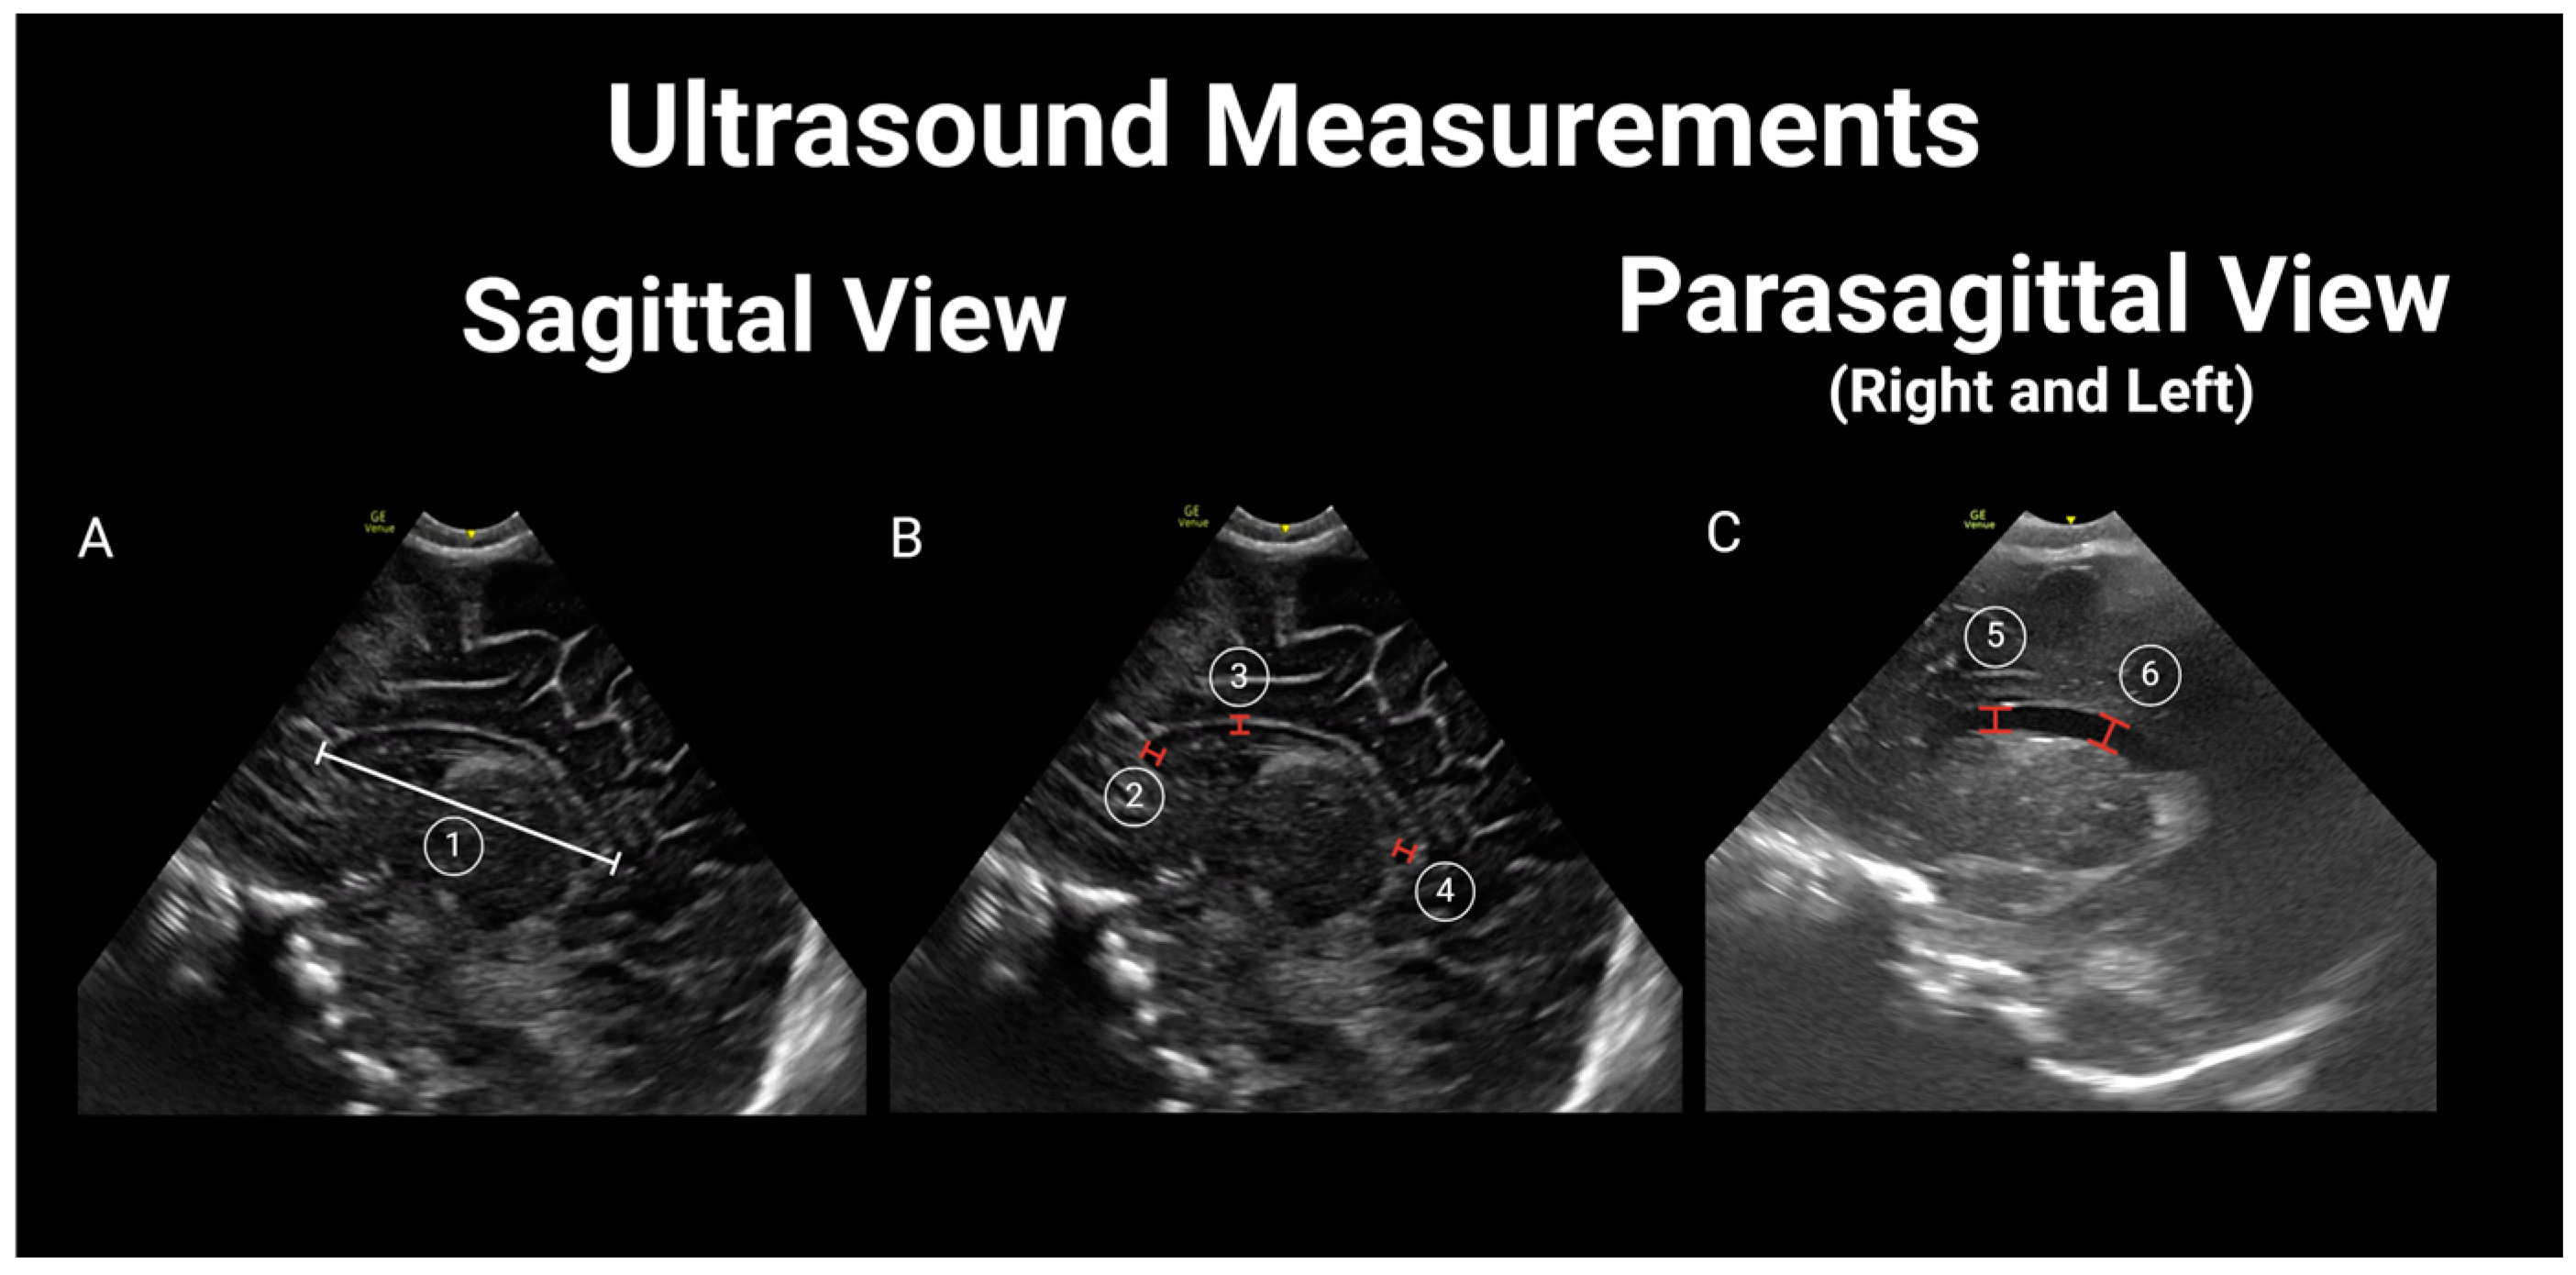

Thereafter, two additional pediatric radiologists (CC and MW), blinded to the newborn’s HIV exposure status, independently reviewed each study to obtain measurements of the lateral ventricles [28] (lateral ventricle anterior horn width—distance between the ventricle walls; lateral ventricular index—distance between the most lateral wall of each ventricle and falx; lateral ventricular transverse width—combined width of both lateral ventricles; ventricle height—vertical diameter of the anterior horn of the lateral ventricle at the apex of the thalamus corresponding to the level of the foramen of Monro; and ventricle midbody height—diameter of the body of the lateral ventricle); biparietal diameter (internal diameter of the skull at the level of the Sylvian fissure); and corpus callosum (corpus callosum length, corpus callosum genu width, corpus callosum body height, and corpus callosum splenium width) [29]. For further details, see Figure 2 and Figure 3. Differences of more than 2 mm in any measurements between the two reviewers were resolved by a third pediatric radiologist (XX) who was also blinded to the newborn’s HIV exposure status.

Figure 3.

Ultrasound measurements in sagittal and parasagittal view. (A) 1. Corpus callosum length (CCL); (B) 2. Corpus callosum genu width (CCGW); 3. Corpus callosum body height (CCBH); 4. Corpus callosum splenium width (CCSW); (C) 5. Vertical height (VH); 6. Ventricle midbody height (VMH).